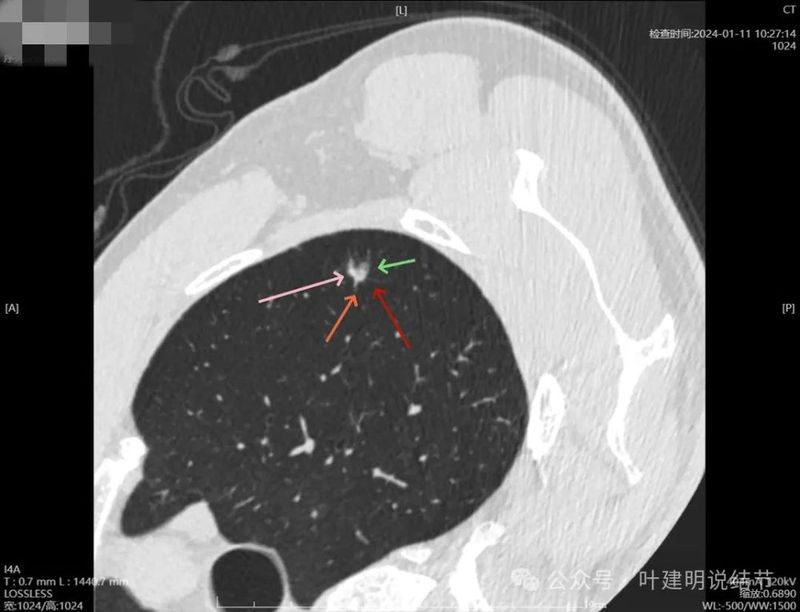

2024年1月靶重建:

病灶密度较高,有月牙铲征,轮廓显模糊。

有微小血管,密度较高,有偏实性成分,磨玻璃密度淡,边界稍糊。

似乎密度过高,毛刺不是太锐利。

密度太高,而且偏长条状。

边缘区密度高,条状。

实性部分密度过高,磨玻璃部分密度淡且瘤肺边界不太清。